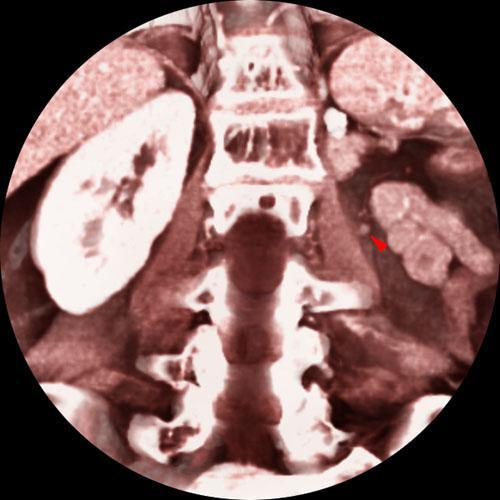

Recidiva local de hipernefroma

VR seccional. Visión coronal anterior. TC contrastado en fase venosa, apreciándose una pequeña lesión nodular (punta de flecha), captante de contraste y pegada al músculo psoas, correspondiente a recidiva del hipernefroma